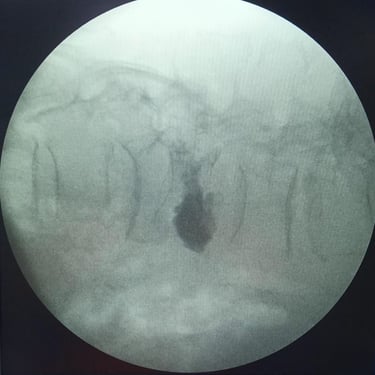

Fractura Lumbar Osteoporótica / Vertebroplastía y Bloqueo Lumbar Selectivo

La fractura lumbar osteoporótica y la artrosis lumbar son causas frecuentes de dolor crónico y limitación funcional en el adulto mayor. La osteoporosis debilita las vértebras, favoreciendo fracturas incluso ante esfuerzos mínimos, mientras que la artrosis genera desgaste articular e inflamación. La vertebroplastía percutánea permite estabilizar las vértebras fracturadas mediante la inyección de cemento óseo, proporcionando alivio rápido y mejorando la movilidad. En casos de dolor persistente por artrosis, el bloqueo lumbar selectivo ayuda a reducir la inflamación y el dolor. Ambas técnicas son procedimientos mínimamente invasivos que mejoran la calidad de vida y facilitan la recuperación funcional.